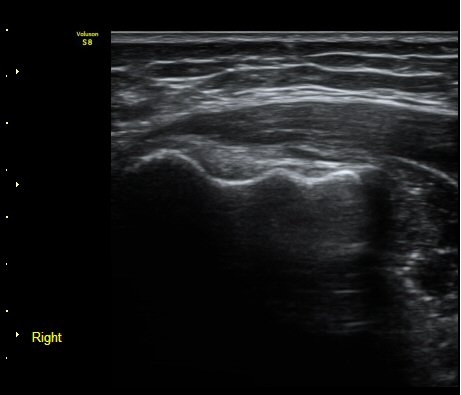

³»»ó°ú Á¾´Ü¸é°Ë»ç»ó  ³»ÃøºÎÀδë Àú¿¡ÄÚ ºÎÁ¾°ú ³»»ó°ú ÀÎ´ë ºÎÂøºÎ ÇÇÁú°ñÀÇ ºÒ±ÔÄ¢º¯È­¿Í

°ñÆíÀÌ °üÂûµÇ°í(±×¸² 1, 2, 3, 4) ÀÌ·±¼Ò°ßÀº °ÇÃø°ú ºñ±³ÇÏ¸é ´õ¿í ¶Ñ·ÈÇÔ(±×¸² 5, 6).